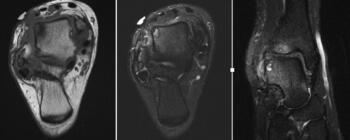

Her initial injury radiographs revealed a small lucent area of the talar dome consistent with an osteochondral defect. Radiographs three months later revealed a more distinct osteochondral defect with a detached fragment of the lateral dome. The MRI was consistent with the radiographs, showing the detached fragment, corresponding bone edema and lateral ligament injury.

New radiographs revealed a small lucent area of the lateral talar dome but no loose body or fragment. Treatment included non-steroidal anti-inflammatory drugs (NSAIDs) and bracing. A month later with no relief, we ordered a new MRI, which revealed an increased number of cystic changes to the lateral talar dome. There was no loose fragment and the cyst areas appeared contained, but it now involved a large area.